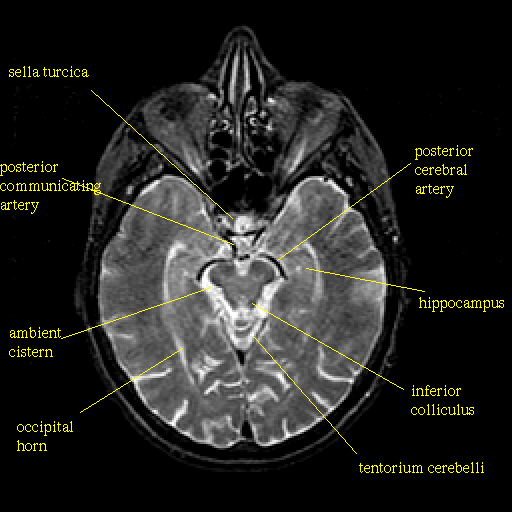

The image below shows a frontal section, that is down on the brain from above, at the level indicate by the small figure to the left of (or if your resolution is low it might show up above) the main image. Clicking on the terms will send you to a definition of the term as it is found in a larger list of Neuropsychological terms [See Note]. If the term is not in the list of definitions, it will return to you to this page.

Images are from the The Whole Brain Atlas.